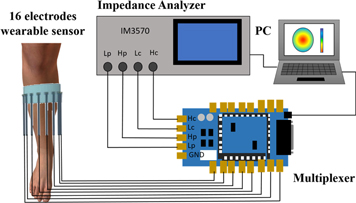

Figure 1 shows the fd-EIT system composed of four units: a wearable sensor consisting of sixteen dry electrodes (Darma et al 2020), a digital multiplexer (made by Takei lab based on Arduino Due), an impedance analyzer (IM3570, HIOKI, Japan), and a PC including image reconstruction algorithm software. The impedance analyzer injects 1 mA sinusoidal current to the electrodes by the adjacent current injection method (Baidillah et al 2019) then measures the impedance Z by way of the digital multiplexer. The impedance analyzer has an impedance measurement accuracy of 0.08% and excitation frequency coverage from 4 Hz to 5 MHz.

Figure 1. fd-EIT system.